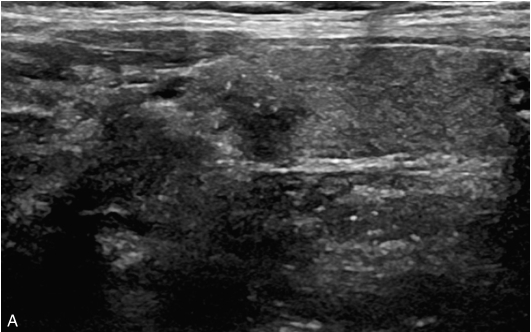

甲状腺右叶中上部见一低回声结节,大小约0.7cm×0.7cm×0.8cm,边界清楚,形态尚规则,内可见少许点状强回声。CDFI示结节内及周边可见较丰富血流信号,见图1-9-5。

图1-9-5 甲状腺髓样癌常规超声声像图

A.甲状腺右叶结节横切面;B.甲状腺右叶结节纵切面;C.甲状腺右叶结节CDFI血流图